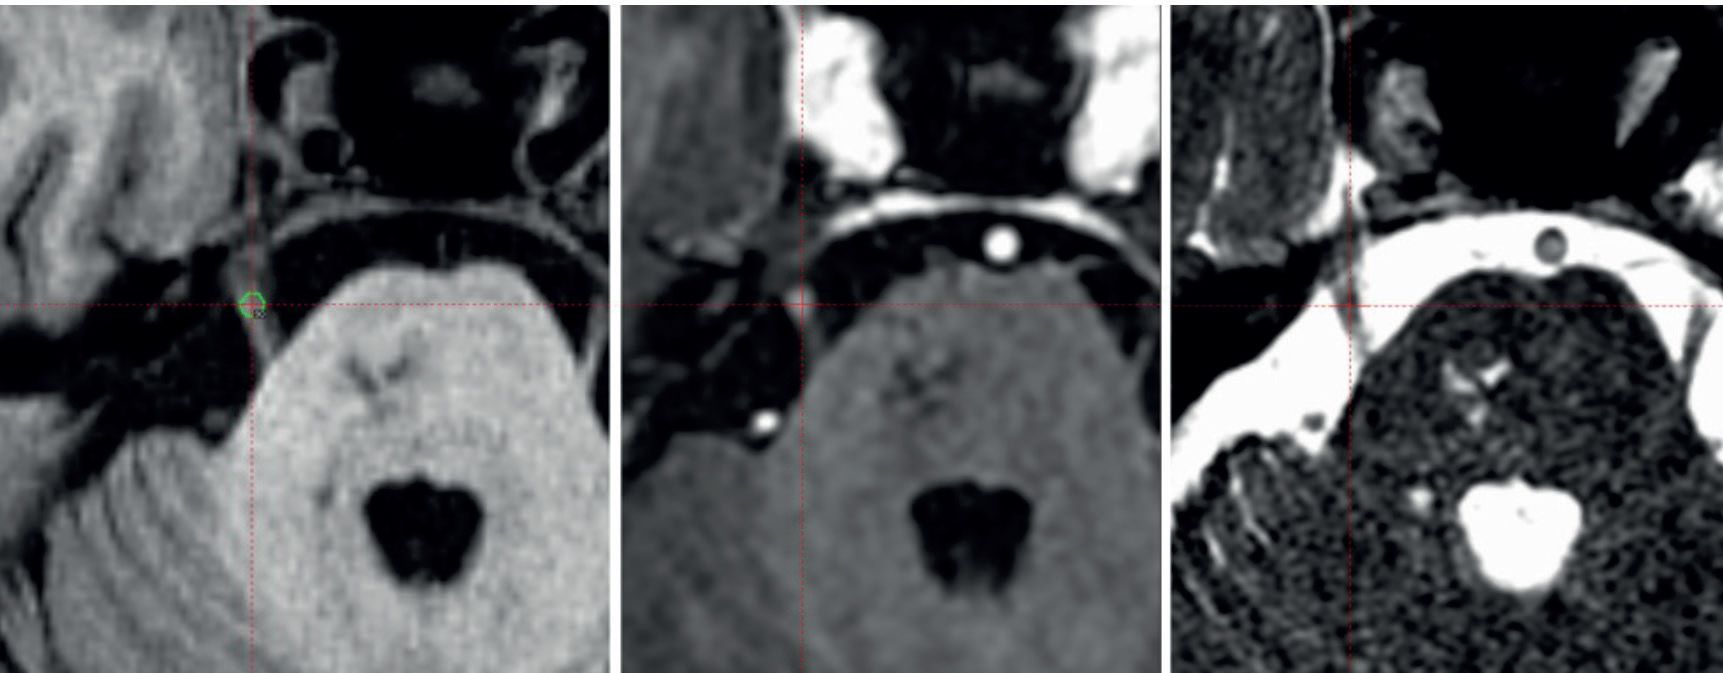

Enhanced visibility of relevant anatomy augments essential accuracy for treating functional indications